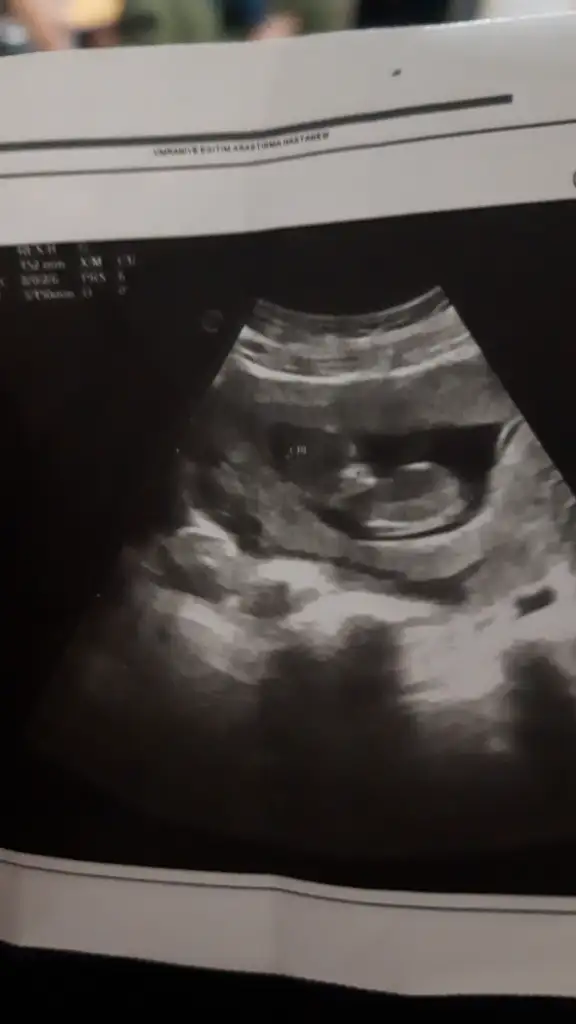

11 haftalık sizce nedir?Erkek sanırım

Bunu kıza benzettim ne zaman öğreneceksiniz11 haftalık sizce nedir?